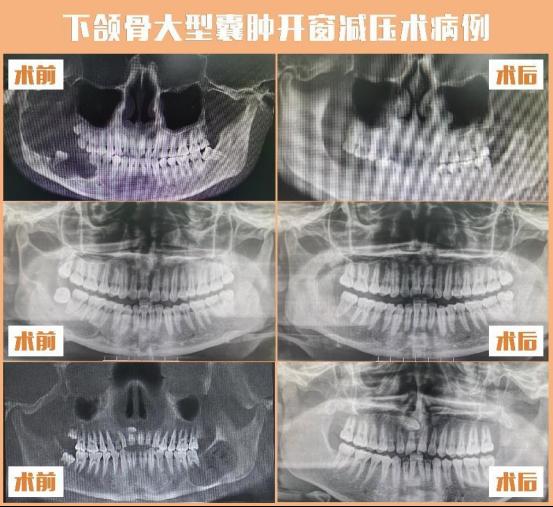

从事口腔颌面外科临床工作10余年,专业特长主要有面部下颌骨偏斜外科治疗,下颌骨前突(地包天)、下颌骨后缩(小下颌)、面部骨骼牵引延长或牙槽骨增高、下颌角宽大(国字脸)的外科治疗;颞下颌关节疾病和关节强直(张口受限);微创拔牙术,如各类复杂阻生牙、埋伏智齿及复杂牙的微创拔除;大型颌骨囊肿的功能外科治疗;牙槽突修整术、牙槽突裂植骨术;口腔颌面部良恶性肿瘤的综合治疗等。

王冬香所在的颅颌面畸形正颌外科团队,是贵州省首家开展正颌外科手术的团队,2018年开展数字化外科设计方案,采用3D打印模型指导手术,使手术更精准,获得面部外形及功能俱佳的治疗效果,其学科水平处于国内领先。王冬香主持开展的院级新技术新项目3D打印塞治器在大型下颌骨囊肿中的应用,遵循功能外科及微创外科的理念,最大限度的保留颌骨外形,创伤小,并发症少,使患者获得更加简单、微创、舒适、经济、有效的治疗。